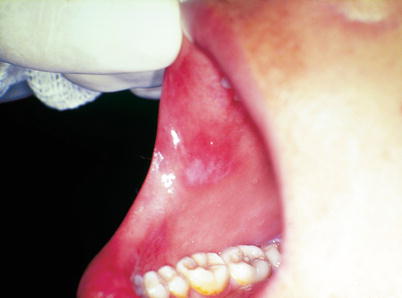

Fig. 2.40

Female patient with an irregular white erythematous plate in the anterior region of the buccal mucosa, a clinical characteristic of secondary syphilis that was confirmed with serological exams (FTA-Abs and VDRL). The patient’s partner presented hard chancre on the penis and on a finger